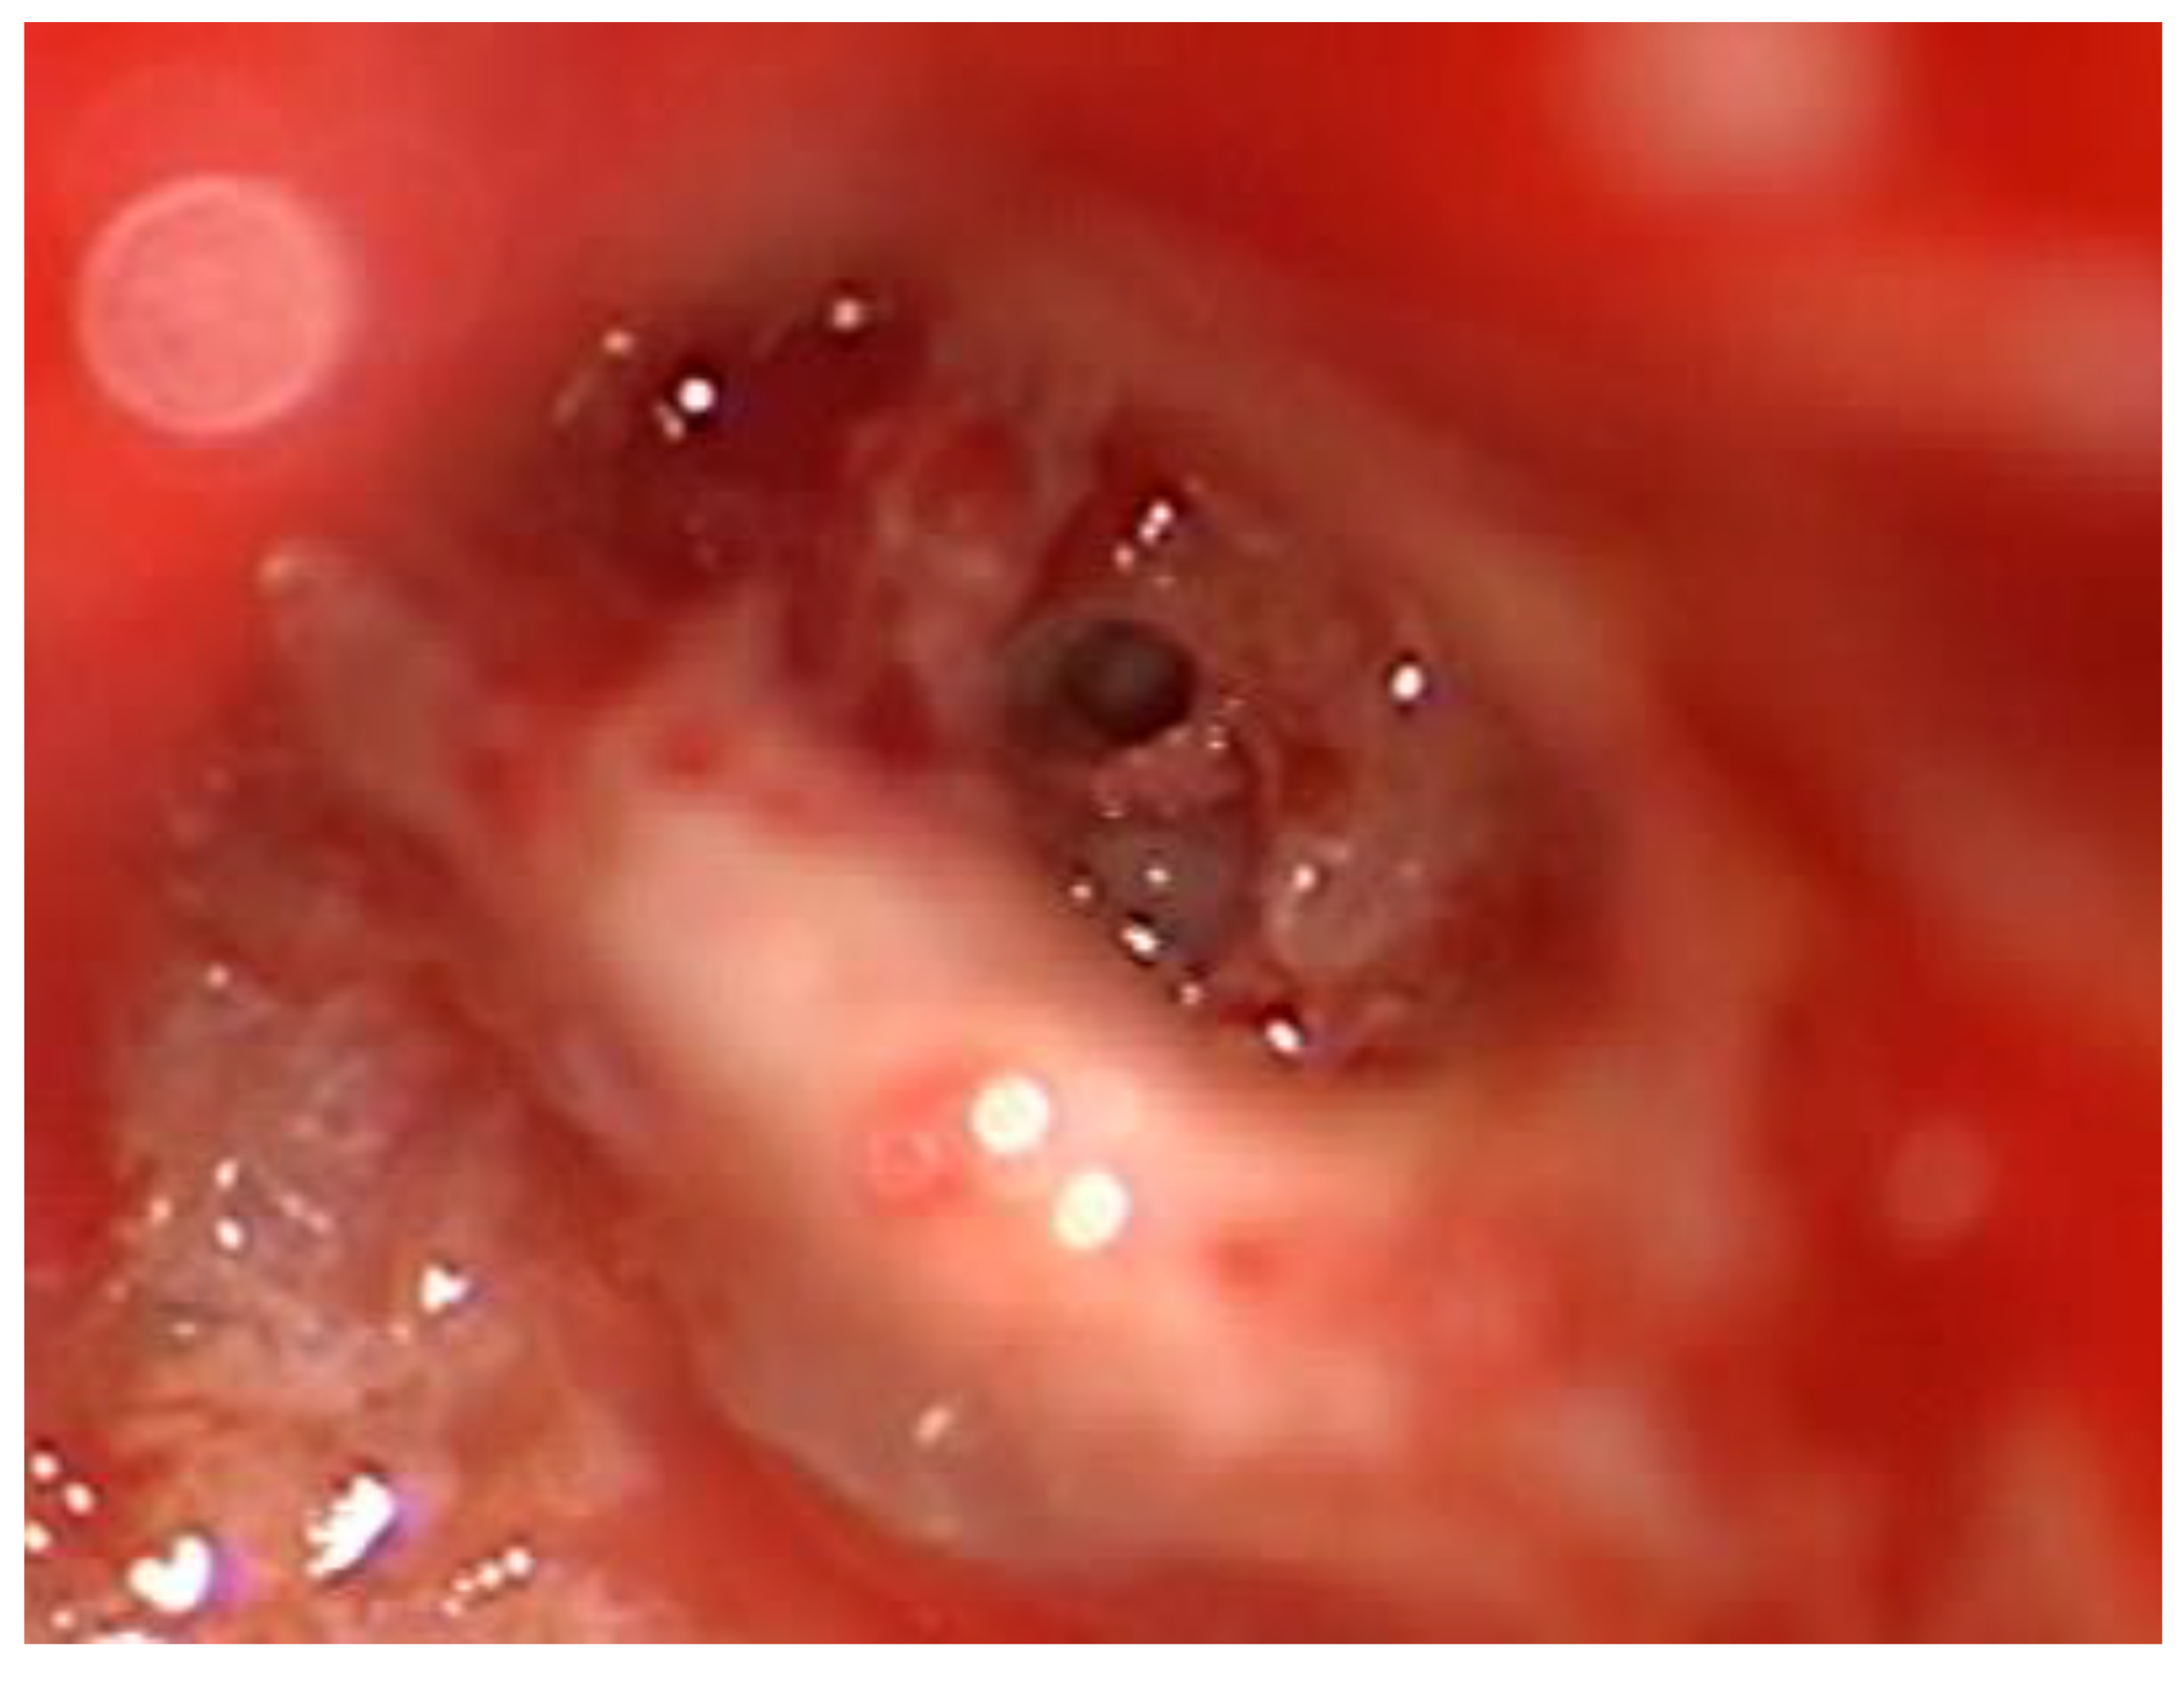

After the removal of parts of the tumor through the enlarged cochleostomy (Figure 1) the TRD was introduced (Figure 2) until the tip was visualized (Figure 3) and carefully grabbed out of the second turn access. By grabbing the tip, the device slipped into the cochleostomy and pushed parts of the tumor out of the second turn. Residual tumor parts could be detached by pipe cleaner handling (Figure 4) and sucked out (Figure 5).

Figure 4. Pipe cleaner handling of the TRD.

Figure 5. Removal of tumor parts (arrow).